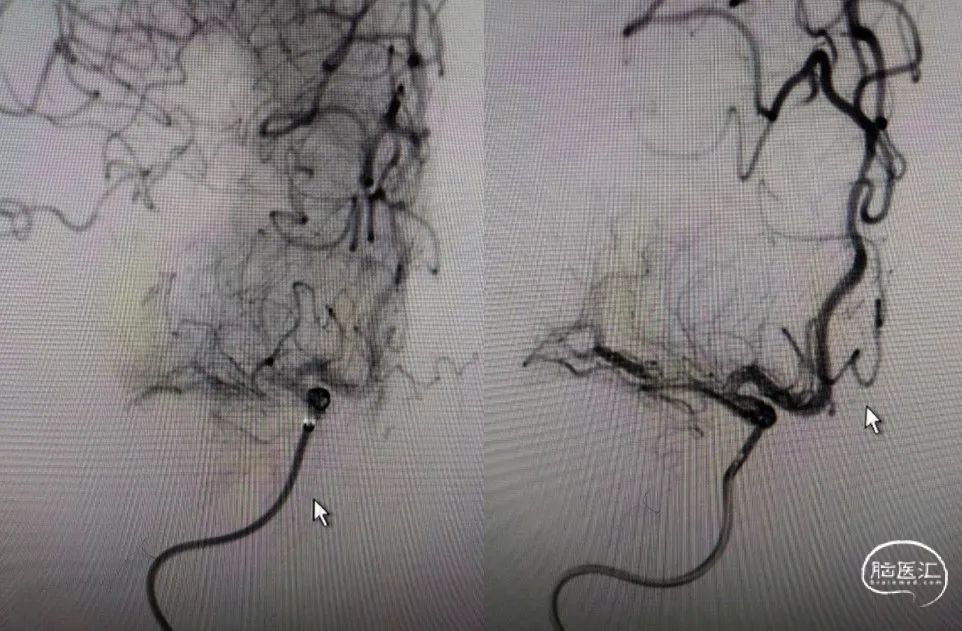

利用PTA球囊导管对狭窄处进行扩张,可见狭窄明显改善,但眼动脉段以后闭塞,再次将取栓支架予以取栓,可见斑块逃逸至M1段。

多次利用取栓支架SWIM技术对逃逸斑块进行取栓但未成功。